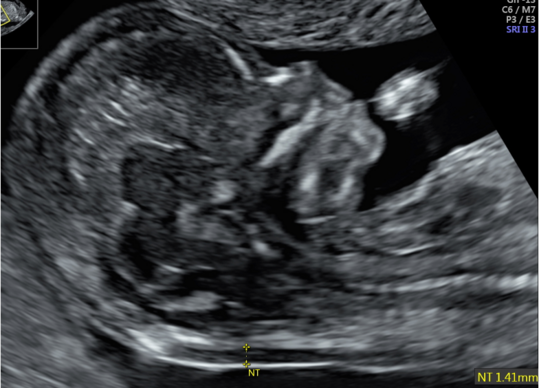

Darstellung der Nackentransparenz bei einem Fetus in 13. SSW

Unter der Nackentransparenz versteht man die mittels Ultraschalls darstellbare Flüssigkeitsansammlung unter der kindlichen Haut im Nackenbereich. Die Dicke dieser Nackenfalte wird zwischen der SSW 11+0 und SSW 13+6 gemessen. Ist diese vergrößert, so ist das Risiko für eine Chromosomenstörung wie zum Beispiel Trisomie 21 (Down-Syndrom) oder bestimmte Fehlbildungen wie etwa Herzfehler erhöht.

Anhand der gemessenen Werte lässt sich mittels einer speziellen Software das individuelle Risiko für die Patientin errechnen. Durch diese Methode können wir in der Pränataldiagnostik und Schwangerenambulanz unter Berücksichtigung des mütterlichen Alters circa 80 Prozent der Kinder mit den schwerwiegendsten Chromosomenstörungen erkennen.

Die Sensitivität kann durch die Kombination mit einer Blutentnahme bei der Mutter zur Bestimmung der Hormone PAPP-A und des freien ß-HCG erhöht werden. Die Entdeckungsrate liegt dann bei circa 90 Prozent. Die Erkennungsrate kann nochmals erhöht werden, indem man im Ultraschall das Nasenbein des Fetus und andere Zusatzparameter (z.B. Ductus venosus) ausmisst.

Das umfangreiche Erst-Trimester-Screening hilft der Patientin bei der Entscheidung für oder gegen eine invasive Diagnostik. Gerade Patientinnen über 35 Jahren, die ein erhöhtes Risiko für eine Trisomie 21 haben, kann so unter Umständen eine invasive Diagnostik erspart bleiben. Das Erst-Trimester-Screening wird in unserer Pränataldiagnostik und Schwangerenambulanz von speziell geschulten, zertifizierten Untersucherinnen und Untersuchern durchgeführt. Im Rahmen der Ultraschalluntersuchung wird der Fetus auch erstmalig auf Fehlbildungen untersucht. Eine ausführliche Feindiagnostik zwischen der 20. und 22. SSW kann diese frühe Ultraschalluntersuchung jedoch nicht ersetzen. In unklaren Fällen oder auf Wunsch der Patienten kann auch eine ergänzende Untersuchung zeIlfreier DNA aus dem mütterlichen Blut ein höheres Maß an Sicherheit erreichen. Ein stufenweises Vorgehen in Abhängigkeit von der Dicke der Nackenfalte wird hierbei empfohlen. Wir beraten Sie hierzu individuell.